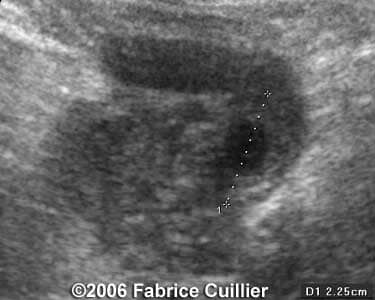

These are some cases of ectopic pregnancy (GEU) using the 2D and 3D scans.